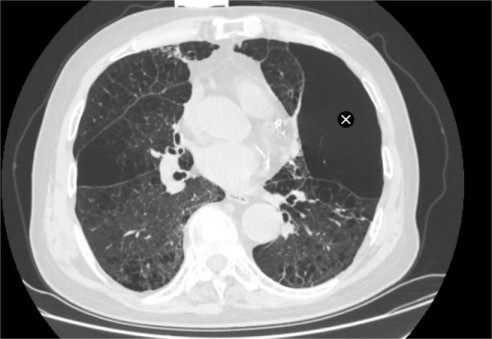

家属带着陈大爷辗转求医,来到苏州大学附属第四医院呼吸内科蒋军红主任门诊就诊。完善胸部CT检查后显示,陈大爷患有异质性肺气肿,肺部病变区域分布极不均衡,部分肺叶过度充气、丧失正常通气功能,形成“无效通气腔”,进一步加重了正常肺组织的负担,这也是他经药物治疗后仍无法缓解症状的核心原因。

该手术并非适用于所有肺气肿患者,精准筛选适宜人群是手术成功的前提。我院团队建立完善的术前评估流程,结合胸部高分辨率CT、肺功能检查、心肺功能评估、叶间裂完整性检测等多项检查,精准判断患者是否为异质性肺气肿,以及病变肺叶位置、肺功能损伤程度。为进一步优化手术方案、规避潜在风险,保障高龄患者手术安全,团队牵头组织术前MDT联合讨论,围绕患者病情、手术适应症、术中风险防控、术后康复方案等核心问题深入研讨、综合研判。